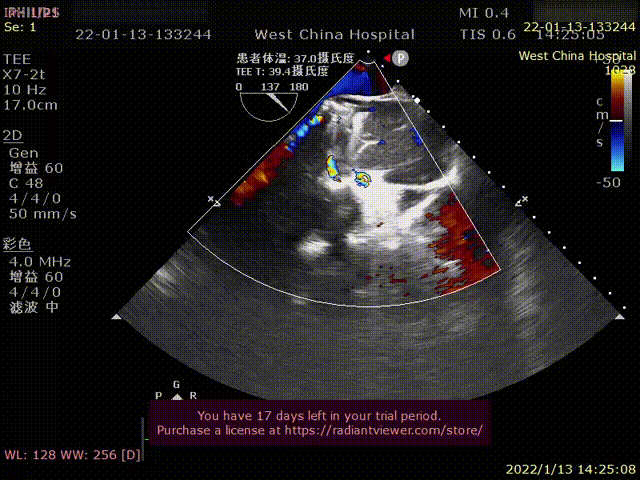

术前超声影像